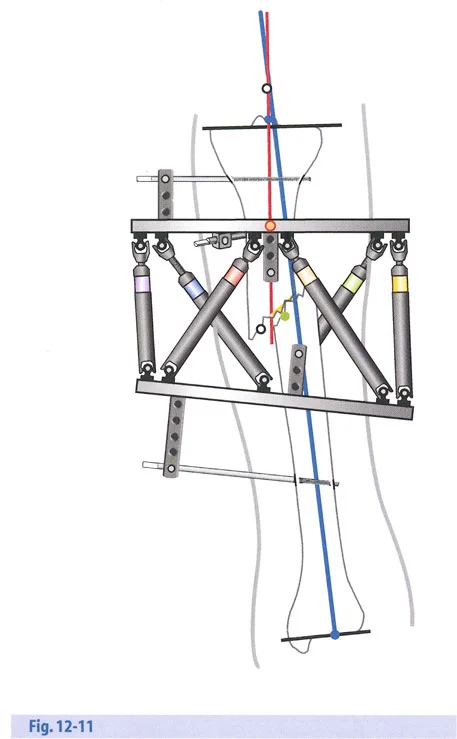

- مثبتات إليزاروف الدائرية الكلاسيكية: تتكون من حلقات معدنية متصلة بالعظم بأسلاك رفيعة، وتسمح بتصحيح متعدد المستويات.

- أنظمة الهيكسابود الحديثة (مثل جهاز تايلور الفراغي Taylor Spatial Frame): تستخدم ست دعامات متداخلة (struts) متصلة بحلقتين. يتم التحكم فيها بواسطة برنامج حاسوبي يقوم بحساب التعديلات اليومية بدقة فائقة لتصحيح التشوه في ستة اتجاهات.

هذا الدليل الشامل يستعرض الاعتبارات الحاسمة لتطبيق الأجهزة، وتحديد مواضع المفاصل الاصطناعية (المفصلات)، وآليات الشد، والتسلسل الاستراتيجي للتصحيحات التدريجية. سواء كان الجراح يستخدم مثبتات إليزاروف الدائرية التقليدية، أو أنظمة الهيكسابود الحديثة (مثل جهاز تايلور الفراغي Taylor Spatial Frame)، أو المثبتات أحادية الجانب، فإن القواعد الهندسية التي تحكم مركز دوران الانحراف (CORA)، ومحور تصحيح الانحراف (ACA)، وانحراف المحور الميكانيكي (MAD) تظل مطلقة ولا تقبل الخطأ.